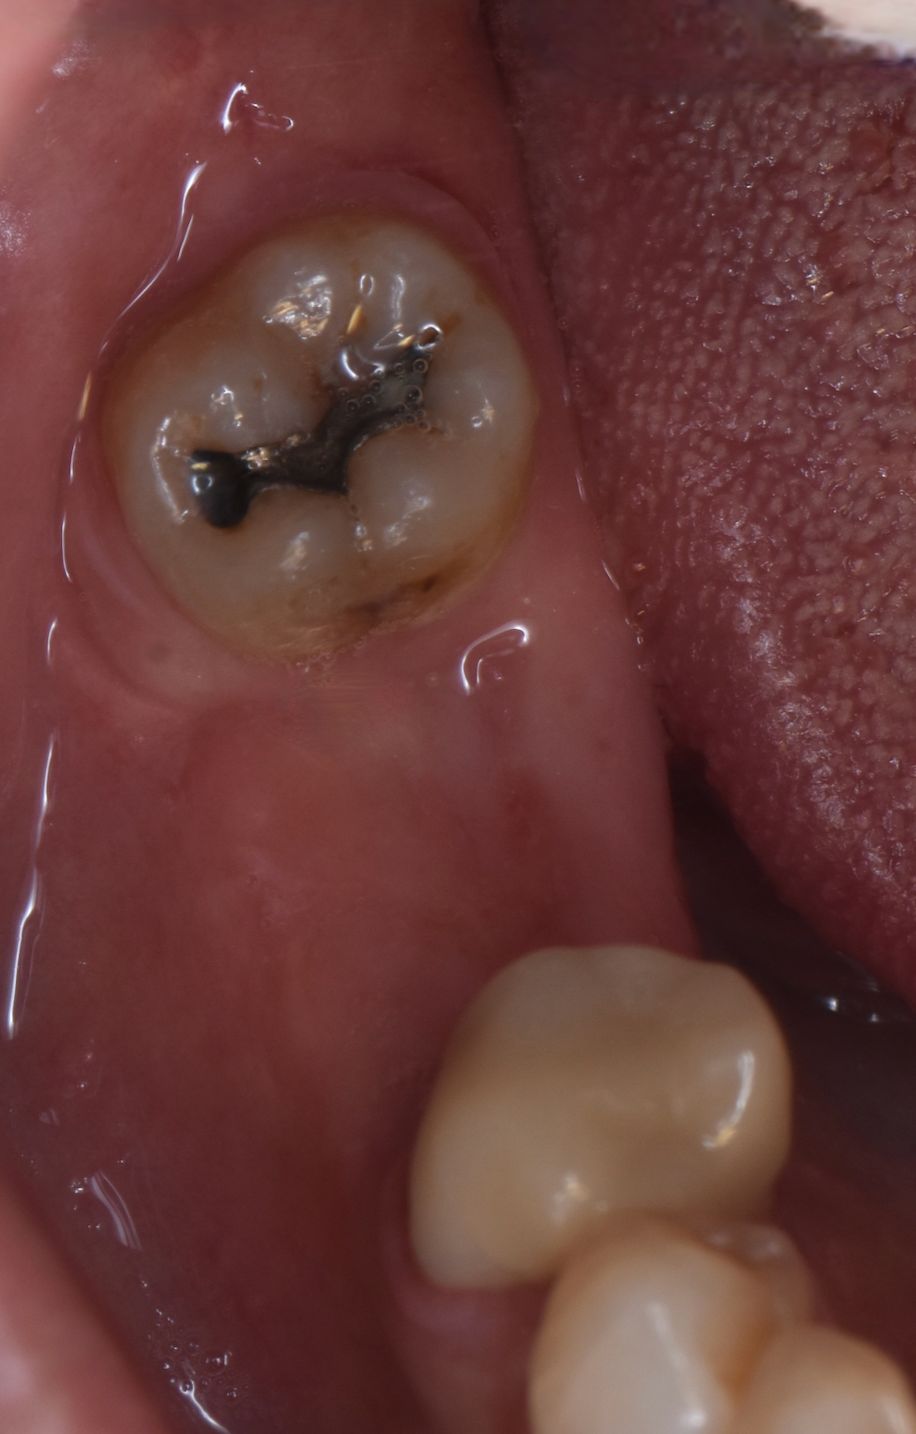

Los implantes dentales son la forma mas estética y funcional de sustituir una diente perdido, ya sea por caries, enfermedad periodontal, traumatismo o agenesia. Lo mas importante para que este tratamiento sea exitoso es su correcta planeación.